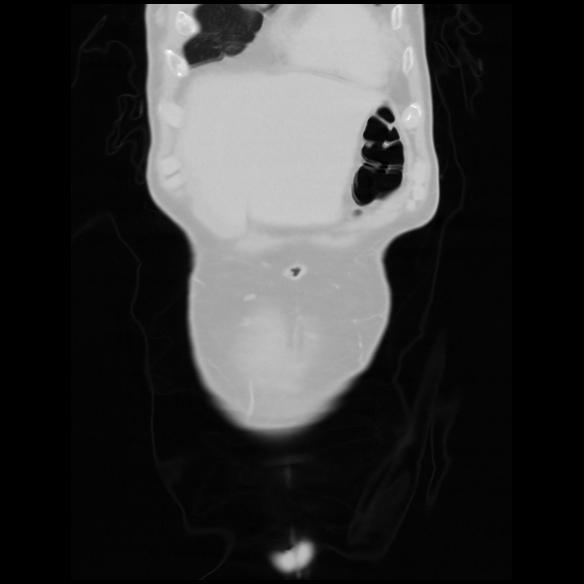

6 CUERPO,CE,Coronal,3.000,CUERPO,Coronal,